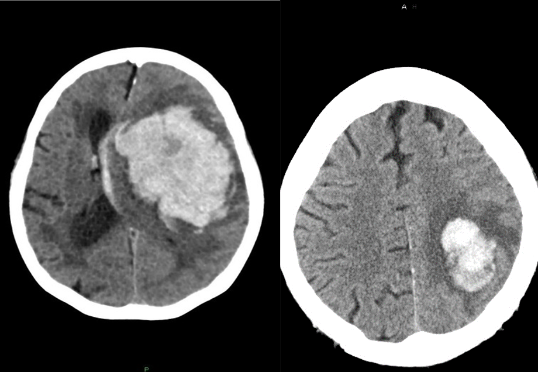

What is this pathology?

Intracerebral Hemmorhage